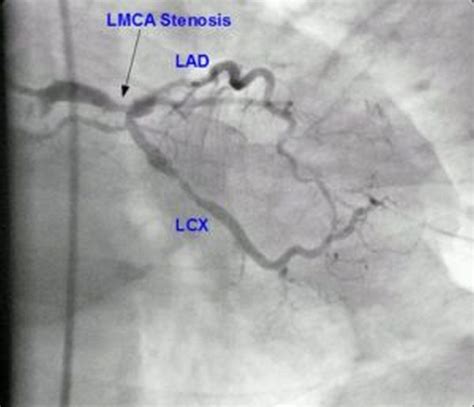

The Clinical Significance of Left Main Disease

When we discuss “Left Main disease,” we are referring to the narrowing or blockage of this critical artery, usually due to atherosclerosis—the buildup of plaque consisting of fats, cholesterol, and other substances. Because the Left Main Artery supplies such a vast territory of the heart muscle, a significant blockage here can result in catastrophic consequences. Unlike blockages in smaller vessels, an obstruction in the main trunk affects the flow to both major branches, potentially causing widespread ischemia (lack of oxygen) across the entire left heart.

Because the Left Main Artery is so vital, cardiologists use highly precise diagnostic tools to evaluate the extent of any blockage. These tests allow doctors to map out the severity of the stenosis and decide on the most appropriate surgical or non-surgical intervention.

Coronary Angiogram The "gold standard" for imaging the lumen of the artery. Very High